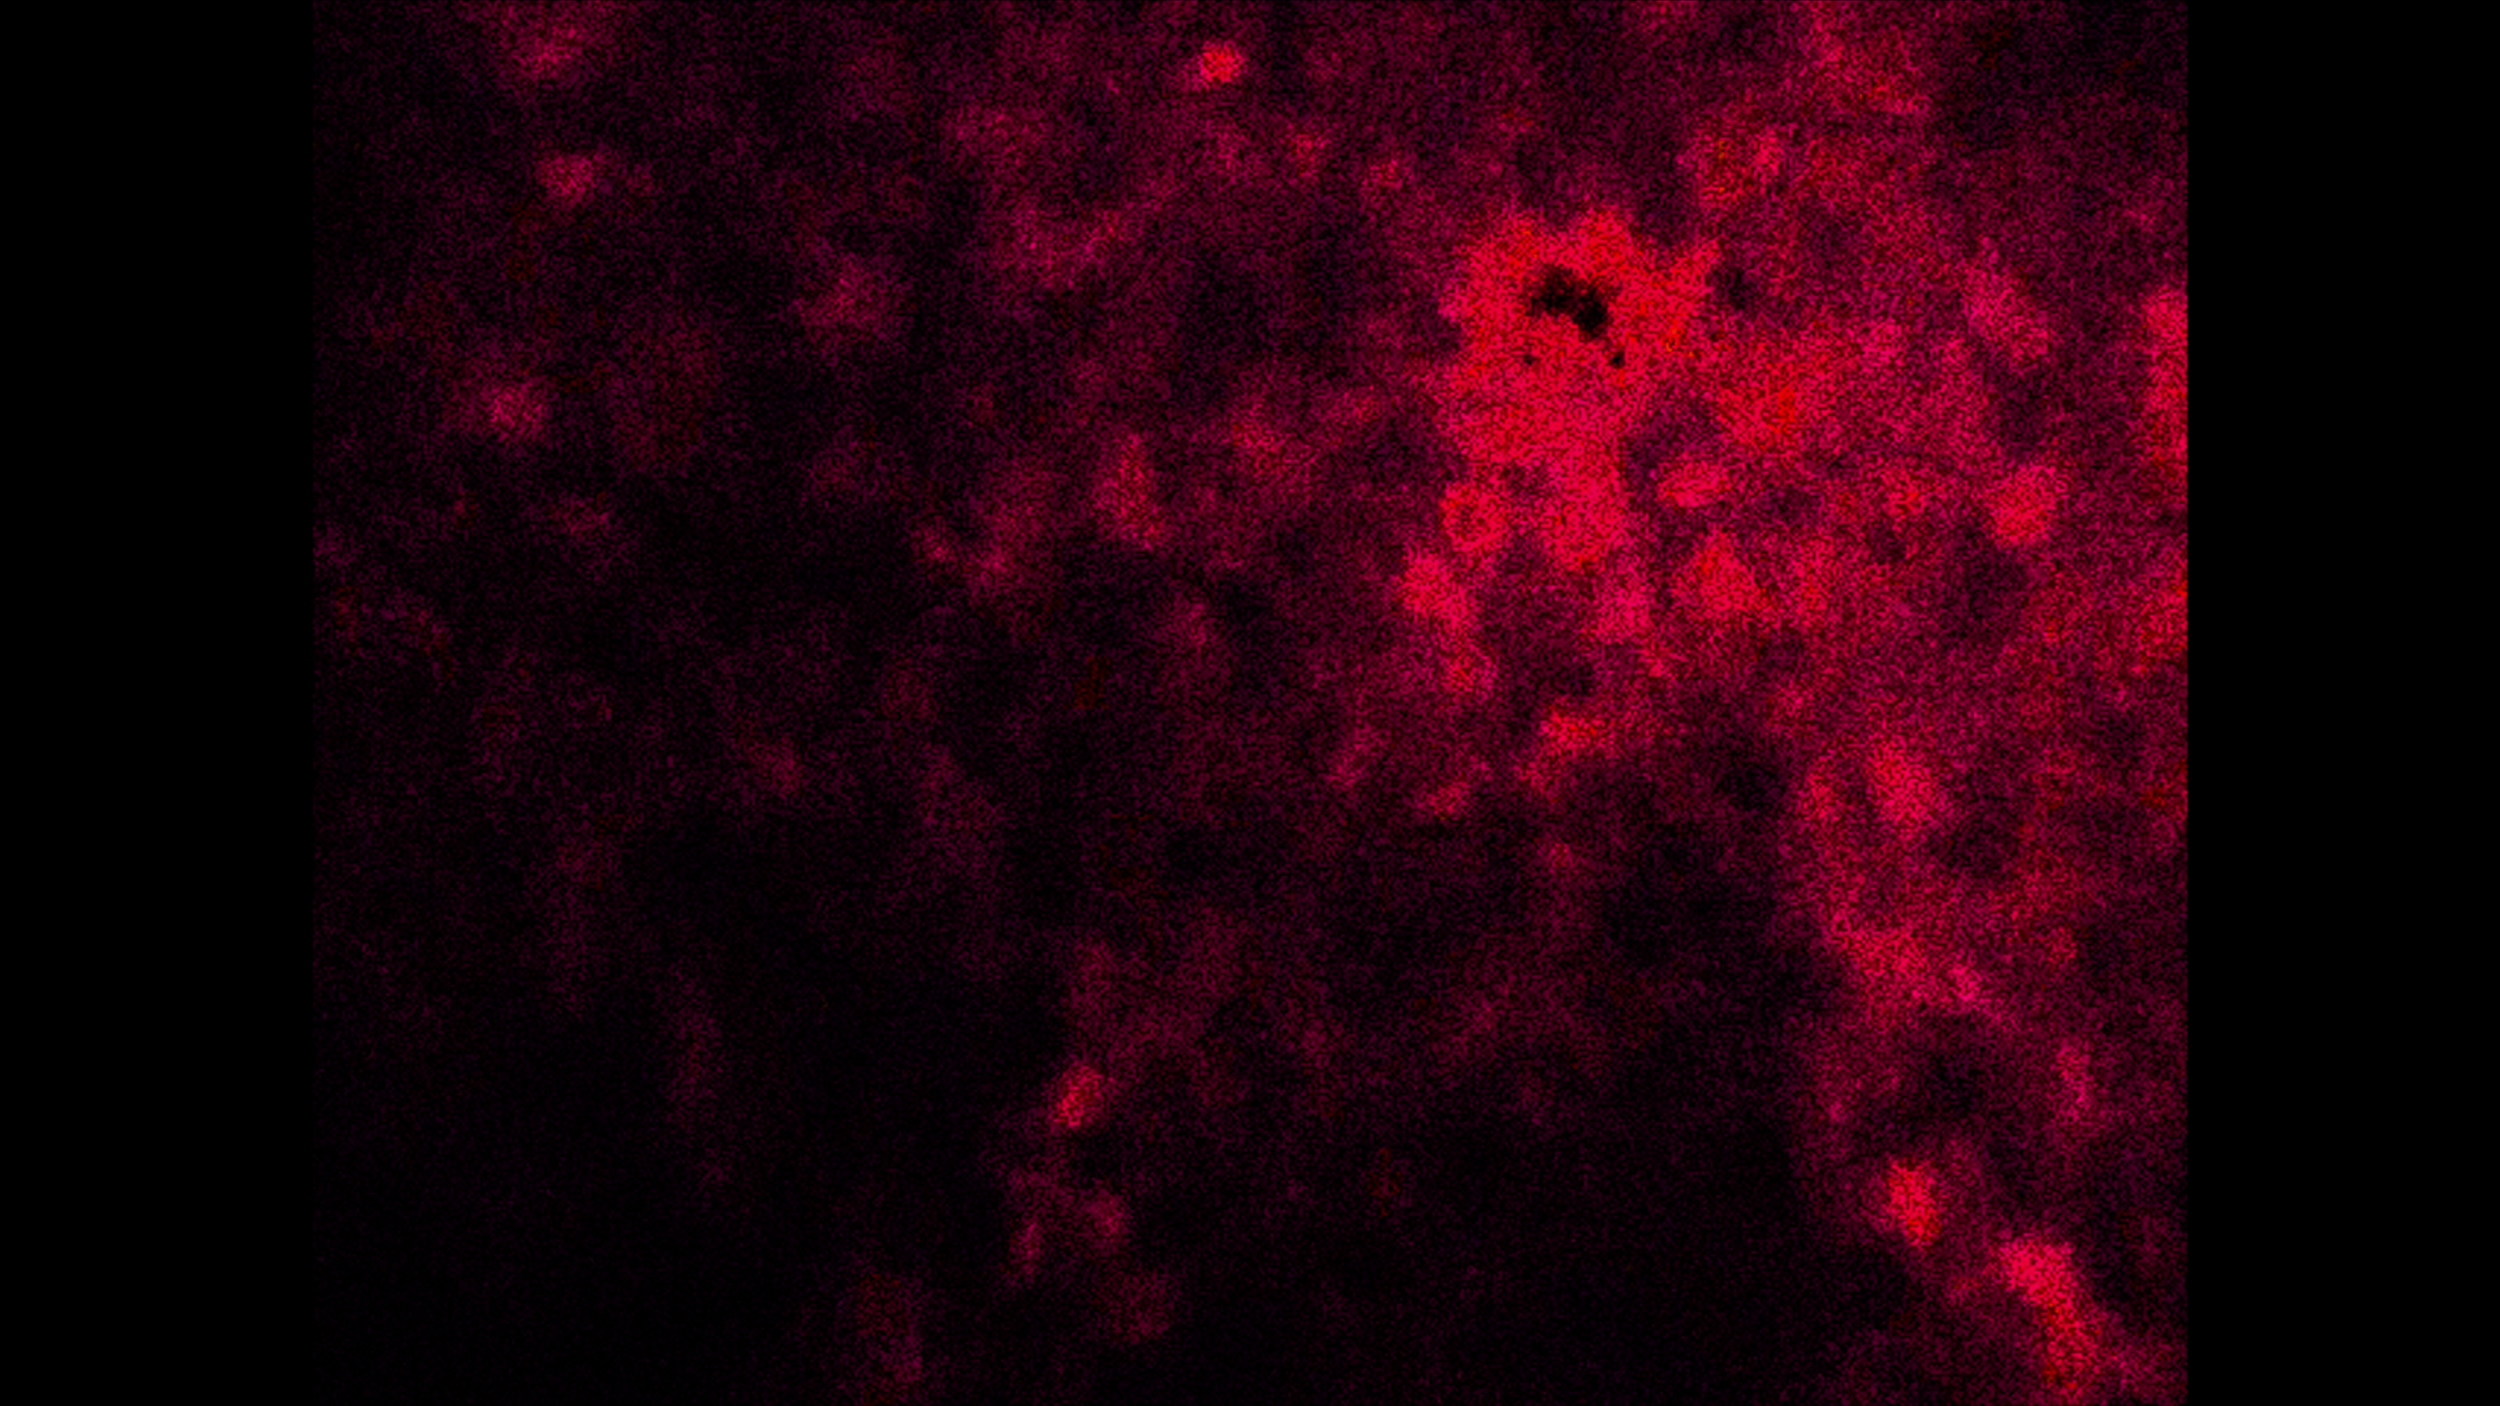

UMRDGM

View Video